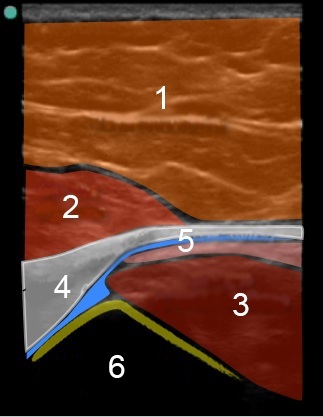

Imagen de la bolsa trocantérica en el lateral de la cadera con la anatomía destacada

1. Grasa subcutánea

2. Músculo glúteo mayor

3. Músculo glúteo medio

4. Músculo tensor de la fascia lata

5. Interfase bursal

6. Corteza del trocánter mayor